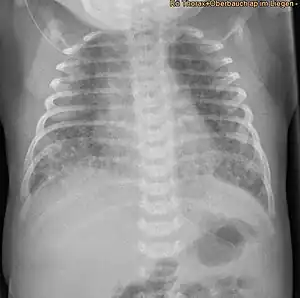

-

Bilateral pneumothorax seen in a newborn with meconium aspiration -

The lung areas which do not or only partially participate in ventilation, because of obstruction and/or destruction, will become hypoxic and an inflammatory response may consequently occur. Partial obstruction will lead to air trapping and hyperinflation of certain lung areas and pneumothorax may follow. Chronic hypoxia will lead to an increase in pulmonary vascular smooth muscle tone and persistent pulmonary hypertension causing respiratory and circulatory failure.[11]